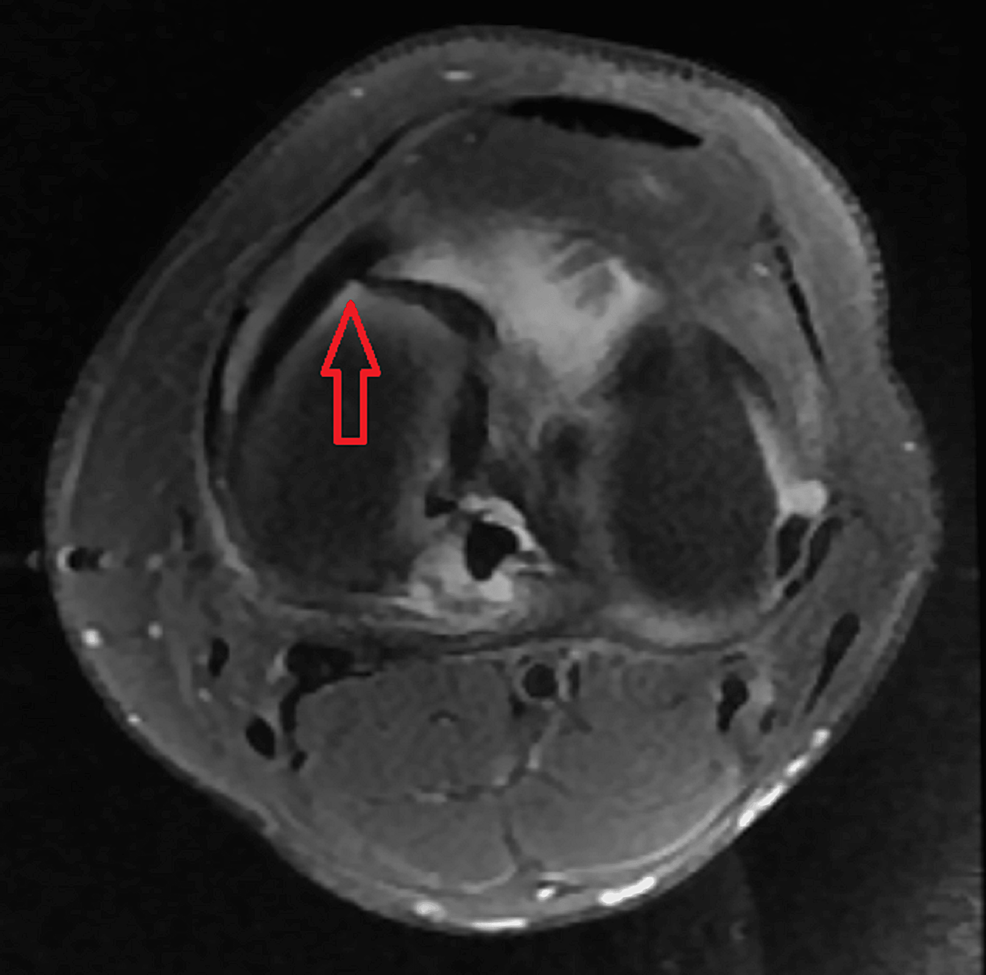

Bucket handle tear

Buckethandle Tear of the Meniscus Radsource What Is A Bucket Handle Tear Definition a bucket handle meniscus tear is a common knee injury that occurs when the meniscus, which is a piece of cartilage in the knee,. These tears often cause the knee to become stuck. According to the journal arthroscopy techniques, an estimated. a bucket handle tear is a type of meniscus tear that affects your knee. What Is A Bucket Handle Tear Definition.

Cureus MRI in the Diagnosis of Bucket Handle Tears What Is the What Is A Bucket Handle Tear Definition These tears often cause the knee to become stuck. a bucket handle tear is a type of meniscus tear that affects your knee. According to the journal arthroscopy techniques, an estimated. a bucket handle meniscus tear is a common knee injury that occurs when the meniscus, which is a piece of cartilage in the knee,. What Is A Bucket Handle Tear Definition.